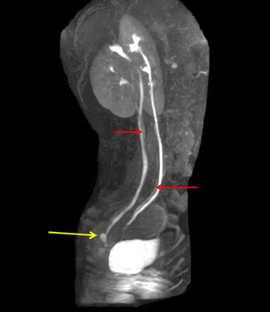

Dueñas-Garcia, O.F., Hall, C.D. Vaginal ectopic ureter simulating preterm premature rupture of membranes. Int Urogynecol J 27, 1773–1774 (2016). https://doi.org/10.1007/s00192-016-3067-8

- Ectopic ureter

- Preterm rupture of membranes

- Urinary incontinence